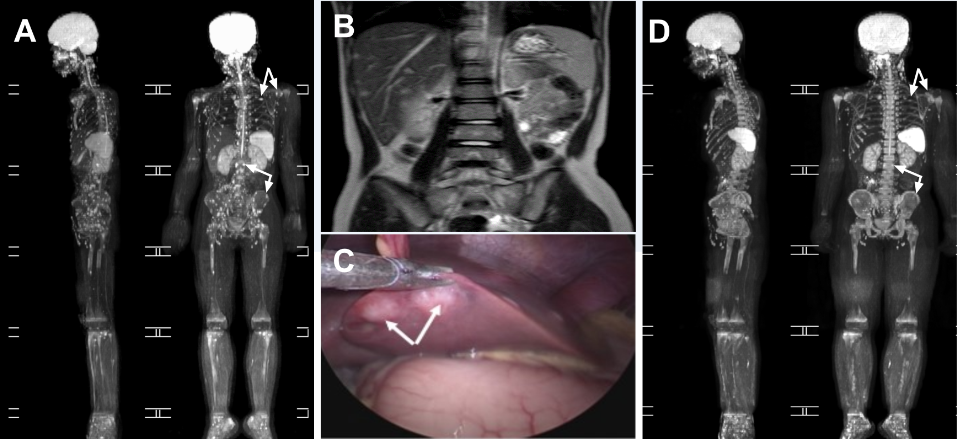

本研究中展示病例为一名反复发热1月余的9岁女孩,MRI扫描时发现全身骨骼异常及肝脾病变,在早期诊断过程中多次被怀疑为恶性肿瘤(图1)。该病例在上海儿童医学中心收治后,经过全面检查排除了其它感染性疾病及肿瘤,根据患儿猫抓史及肝组织活检病理初步判断为猫抓病,随后通过农业生物学院袁聪俐团队进行间接免疫荧光、免疫组织免疫化学、核酸检测等不同技术对病患血清及受累器官进行巴尔通体感染检测,最终确诊为急性播散性猫抓病(图2)。

图1. 汉塞巴尔通体感染所致全身骨骼损害及内脏损害(A、B、C),经多西环素治疗6周后全身骨骼损害恢复情况(D)